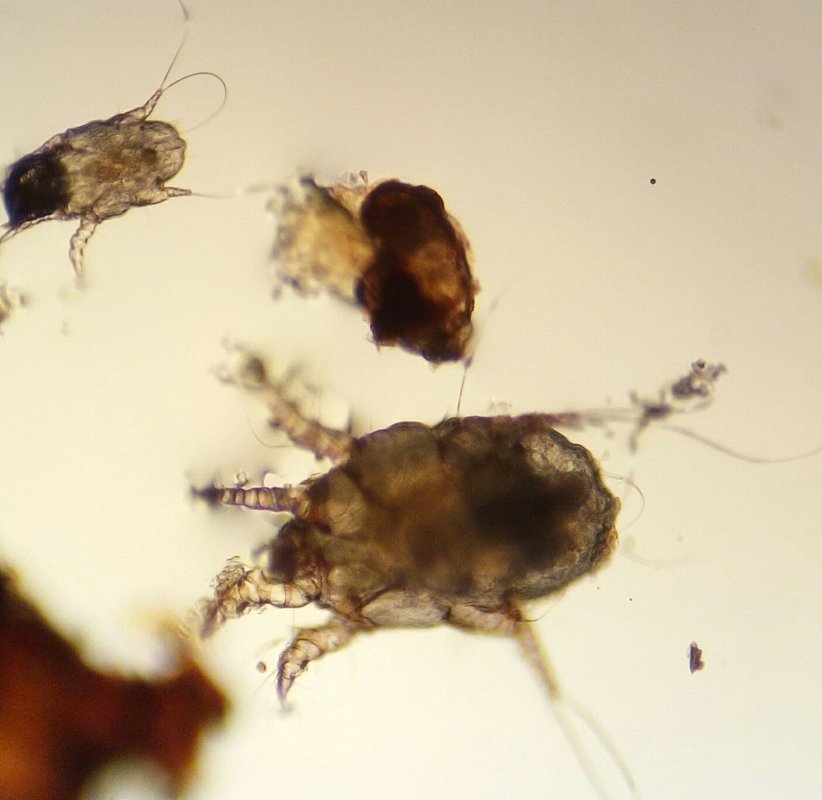

Мы также располагаем кадрами и оборудованием для проведения лабораторных анализов. Имея на руках результаты исследований, доктор будет объективен, назначая лекарства и процедуры. Это в особенности актуально при лечении животных, ведь они не имеют возможности рассказать нам о своих симптомах!

Среди наших услуг анализ крови, анализы на панлейкопению, пироплазмоз, токсоплазмоз, УЗИ, анестезия, вакцинация кошек, собак и кроликов, вакцинация против бешенства, взвешивание животных, дегельминтизация кошек и собак, кастрация, проведение кесарева сечения, купирование хвоста, обработка от блох, прием родов у животных, стерилизация, удаление зубного камня, удаление зубов, извлечение клещей, уколы, чистка зубов, услуги груминга (в том числе маникюр, подстригание когтей, стрижка и чистка ушей), эвтаназия животных, приём ветеринарного дерматолога, кардиолога, офтальмолога, стоматолога, терапевта, хирурга, гинеколога и диагноста, оформление ветпаспорта, консультация герпетолога и орнитолога, диспансеризация животных, стационар для животных, лечение грызунов, змей, морских свинок и экзотических животных.